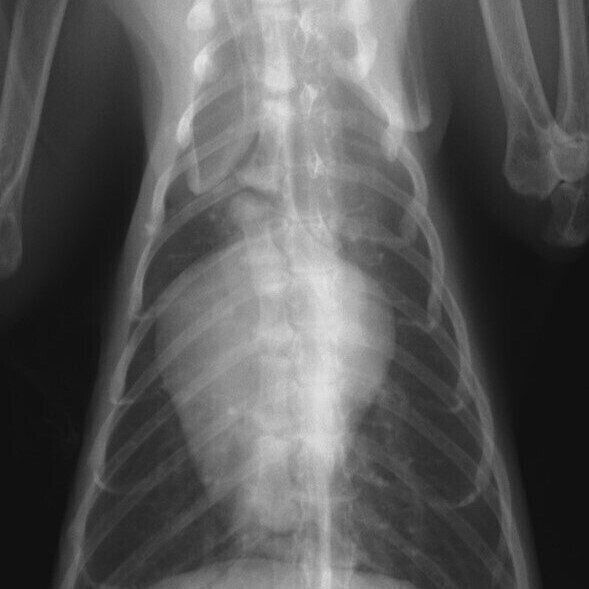

提供/王子ペットクリニック

「肥大型心筋症」のレントゲン写真。左心房が拡大し、心臓が「バレンタインハート」と呼ばれる特徴的なハートの形状になっています。